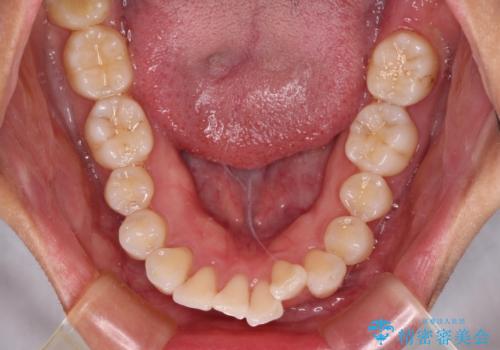

- 飛び出した前歯を気にして来院された患者様です。

口元を引っ込めるために上下左右の第一小臼歯4本を抜歯することとしました。